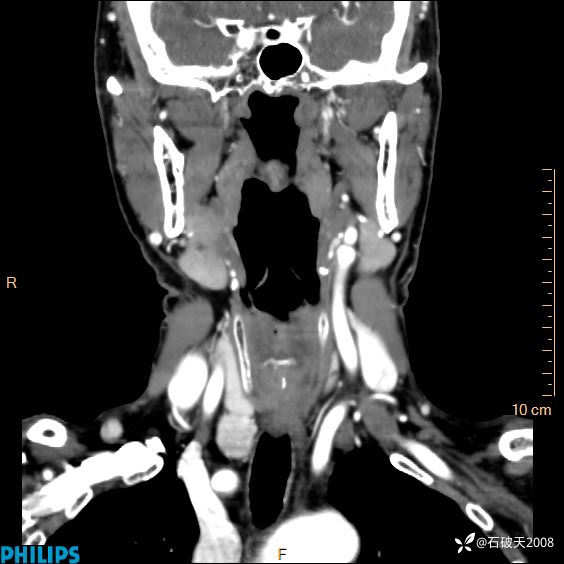

静脉期